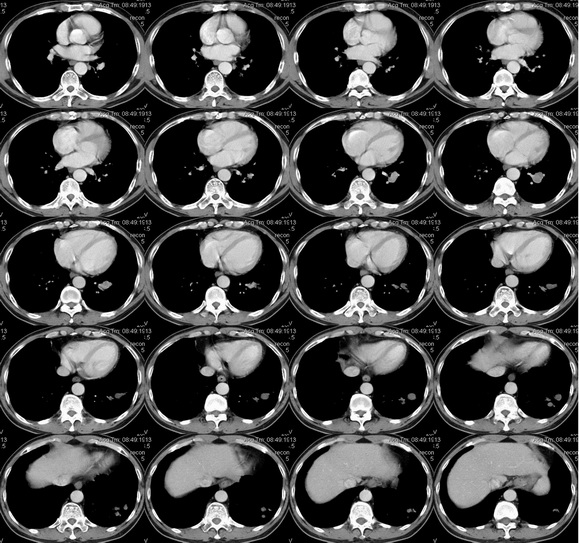

男性 45岁,咳嗽、咳血1月,曾用抗生素治疗10多天。

左下肺结节及肺门结节,增强延时似强化,周围性肺ca?机化性肺炎,建议支纤镜,穿刺

不排除左肺下叶周围型肺癌并左下肺门区淋巴结转移可能。

考虑左肺下叶内基底段肺癌并支气管黏液栓形成或左肺门区淋巴结压迫支气管引起综合征.

考虑左肺下叶内基底段肺癌

考虑左肺下叶内基底段肺癌并支气管黏液栓形成可能;建议随访复查。纤支镜未刷见癌细胞对于否定肺癌参考价值不大。

要看病人既往史,咳嗽时间的长短,咯血量的多少;倾向于考虑为支气管扩张(粘液栓)